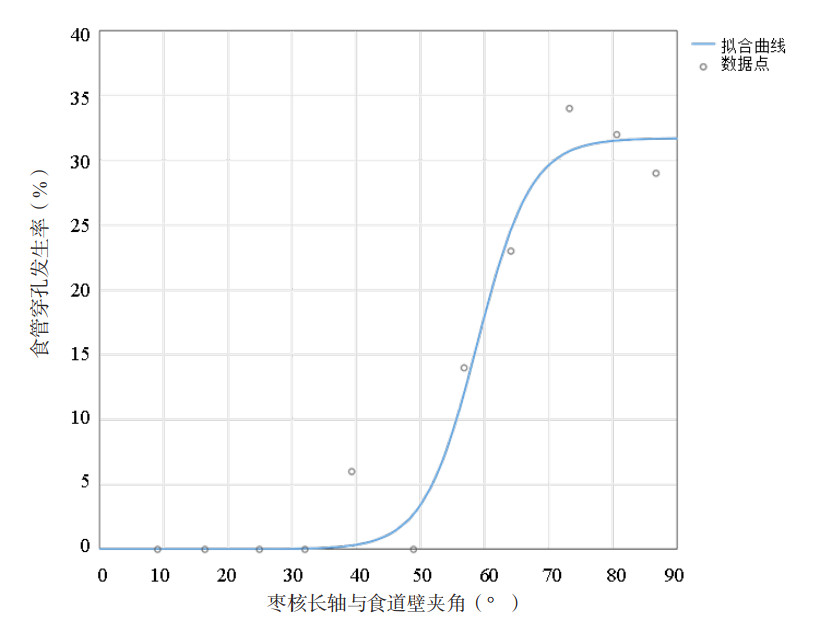

在研究对象中,嵌顿枣核长轴与食管壁夹角分布在6°~89°范围内。每8°为一段将数据分为11段,分别计算每段的夹角均值,并根据公式(1)计算每段内患者的穿孔发生率,见表 4。

其中D表示枣核与食管壁夹角,PD表示食管穿孔的预测概率。拟合曲线见图 4,拟合优度RD2=0.96,均方根误差RMSED=0.030。

| 图 4 枣核长轴与食管壁夹角和食管穿孔发生率的曲线拟合 |

经研究枣核长度、枣核长轴与食管壁夹角均为食管穿孔的危险因素,分别与食管穿孔发生的概率呈一定规律。由公式2可知食管嵌顿枣核长度和发生食管穿孔的概率符合三次多项式模型(RL2=0.93)。由图 3可知穿孔的发生率随枣核长度的增长而增长。由公式3可知枣核与食管夹角的角度和发生食管穿孔的概率符合Logistic模型(RD2=0.96)。由图 4的拟合曲线可知,夹角在40°以内几乎不会发生食管穿孔,40°~70°范围内穿孔发生率随夹角增大而增长,超过70°后维持30%以上的高发生率。值得注意,数据点(39.3°,6.0%)的残差较大(δ=0.057),是由于在37°~45°范围内收集的17例患者中,有1例枣核长轴与食管壁夹角为40°的患者发生了食管穿孔。因此结合拟合曲线和数据点,可将35°设置为低风险临界值,当枣核与食管壁的夹角小于35°时发生穿孔风险较低。70°设置为高风险临界值,当夹角大于70°时发生穿孔的风险较高,应引起足够重视。对于枣核与食管壁夹角在35°~70°范围内的情况,可以参考枣核长度与食管穿孔发生率的关系(公式2)做出进一步判断。